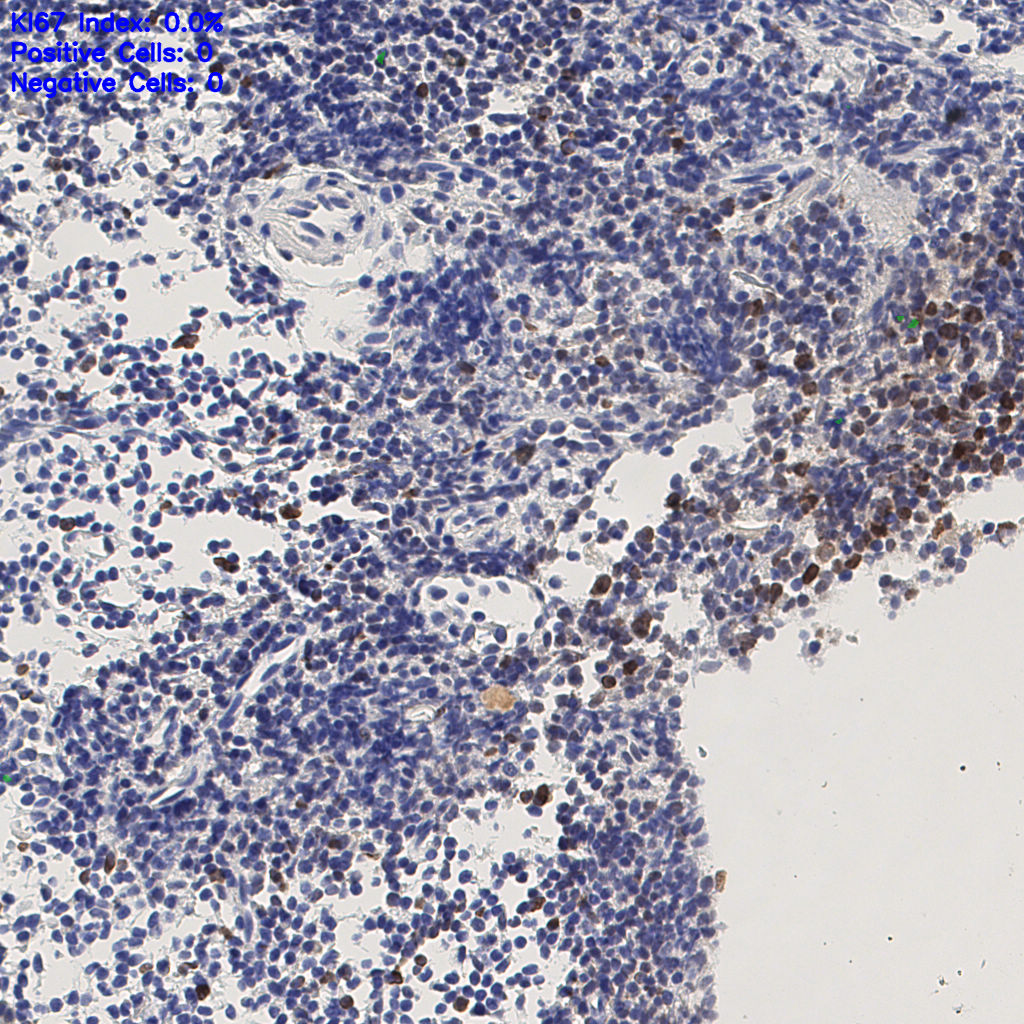

slice_61_16_x54656_y14336.png

slice_61_16_x5465...